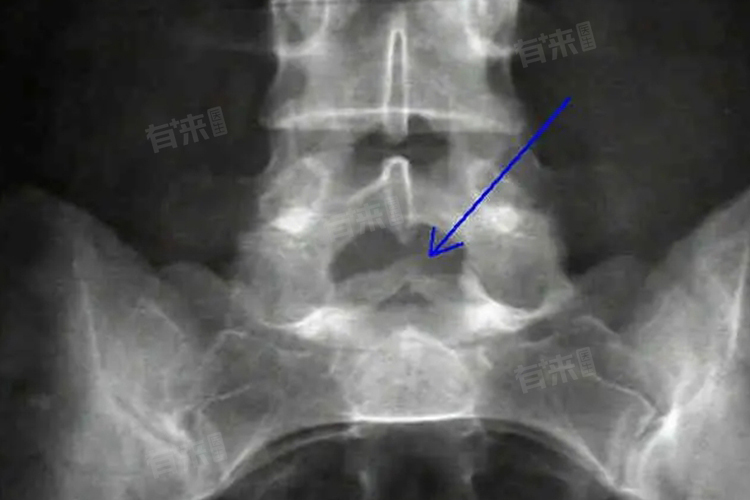

- 儿童骶椎隐裂,也被称为隐性脊柱裂或骶尾部隐裂,是一种较为常见的先天性脊柱发育异常,这种状况指的是在骶骨区域存在一种不完全闭合的现象,但与更为严重的开放性脊柱裂不同,骶椎隐裂通常不会导致明显的神经管缺陷暴露在外。大多数情况下,骶椎隐裂的个体可能没有任何症状,或者仅有轻微的症状,因此许多人在成年后才偶然发现这一情况。

- 一般而言,骶椎隐裂多数情况下可能会在18至20岁之间自然闭合。然而,如果症状较为轻微,这个过程也可能提前到12至14岁就开始显现闭合的趋势,但这些时间框架并非适用于所有人,实际情况会因人而异,受到多种因素的影响,包括遗传背景、营养状况和个人健康状态等。